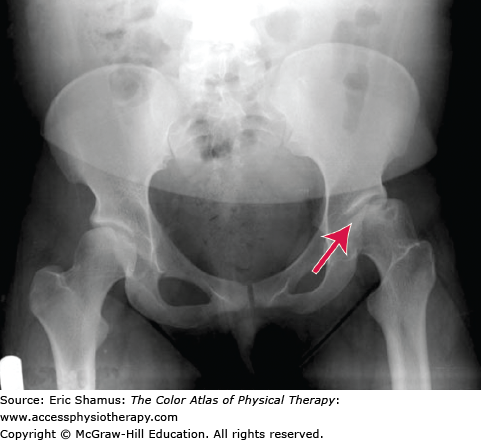

LEGG-CALVE-PERTHÉS DISEASE

An 11-year-old male is referred to physical therapy with a diagnosis of Legg–Calvé–Perthes disease (LCPD). Gait analysis reveals an antalgic gait on the affected left side. The child reports 7/10 pain in the hip and groin and difficulty with ambulation and stair climbing. His passive range of motion (ROM) is limited in left hip internal rotation, abduction, and extension. The parents report use of a Scottish-Rite brace was unsuccessful and the child is scheduled for surgical correction. The physical therapist instructs the child in crutch training pre-op and then provides gait training, RMO exercises, and strengthening post-op.

Answer with rationale: A. Hip Avascular Necrosis (AVN) with possible pathogenesis of injury, synovitis, infection or vascular abnormalities (either inherited or developed). AVN is the basic cause for LCPD, and it can develop from congenital or acquired sources. The AVN leads to destruction/degradation of the hip joint and surrounding structures, including necrosis and deformation. These in turn can lead to the symptoms noted in the patient: antalgic gait, pain, and limited mobility.